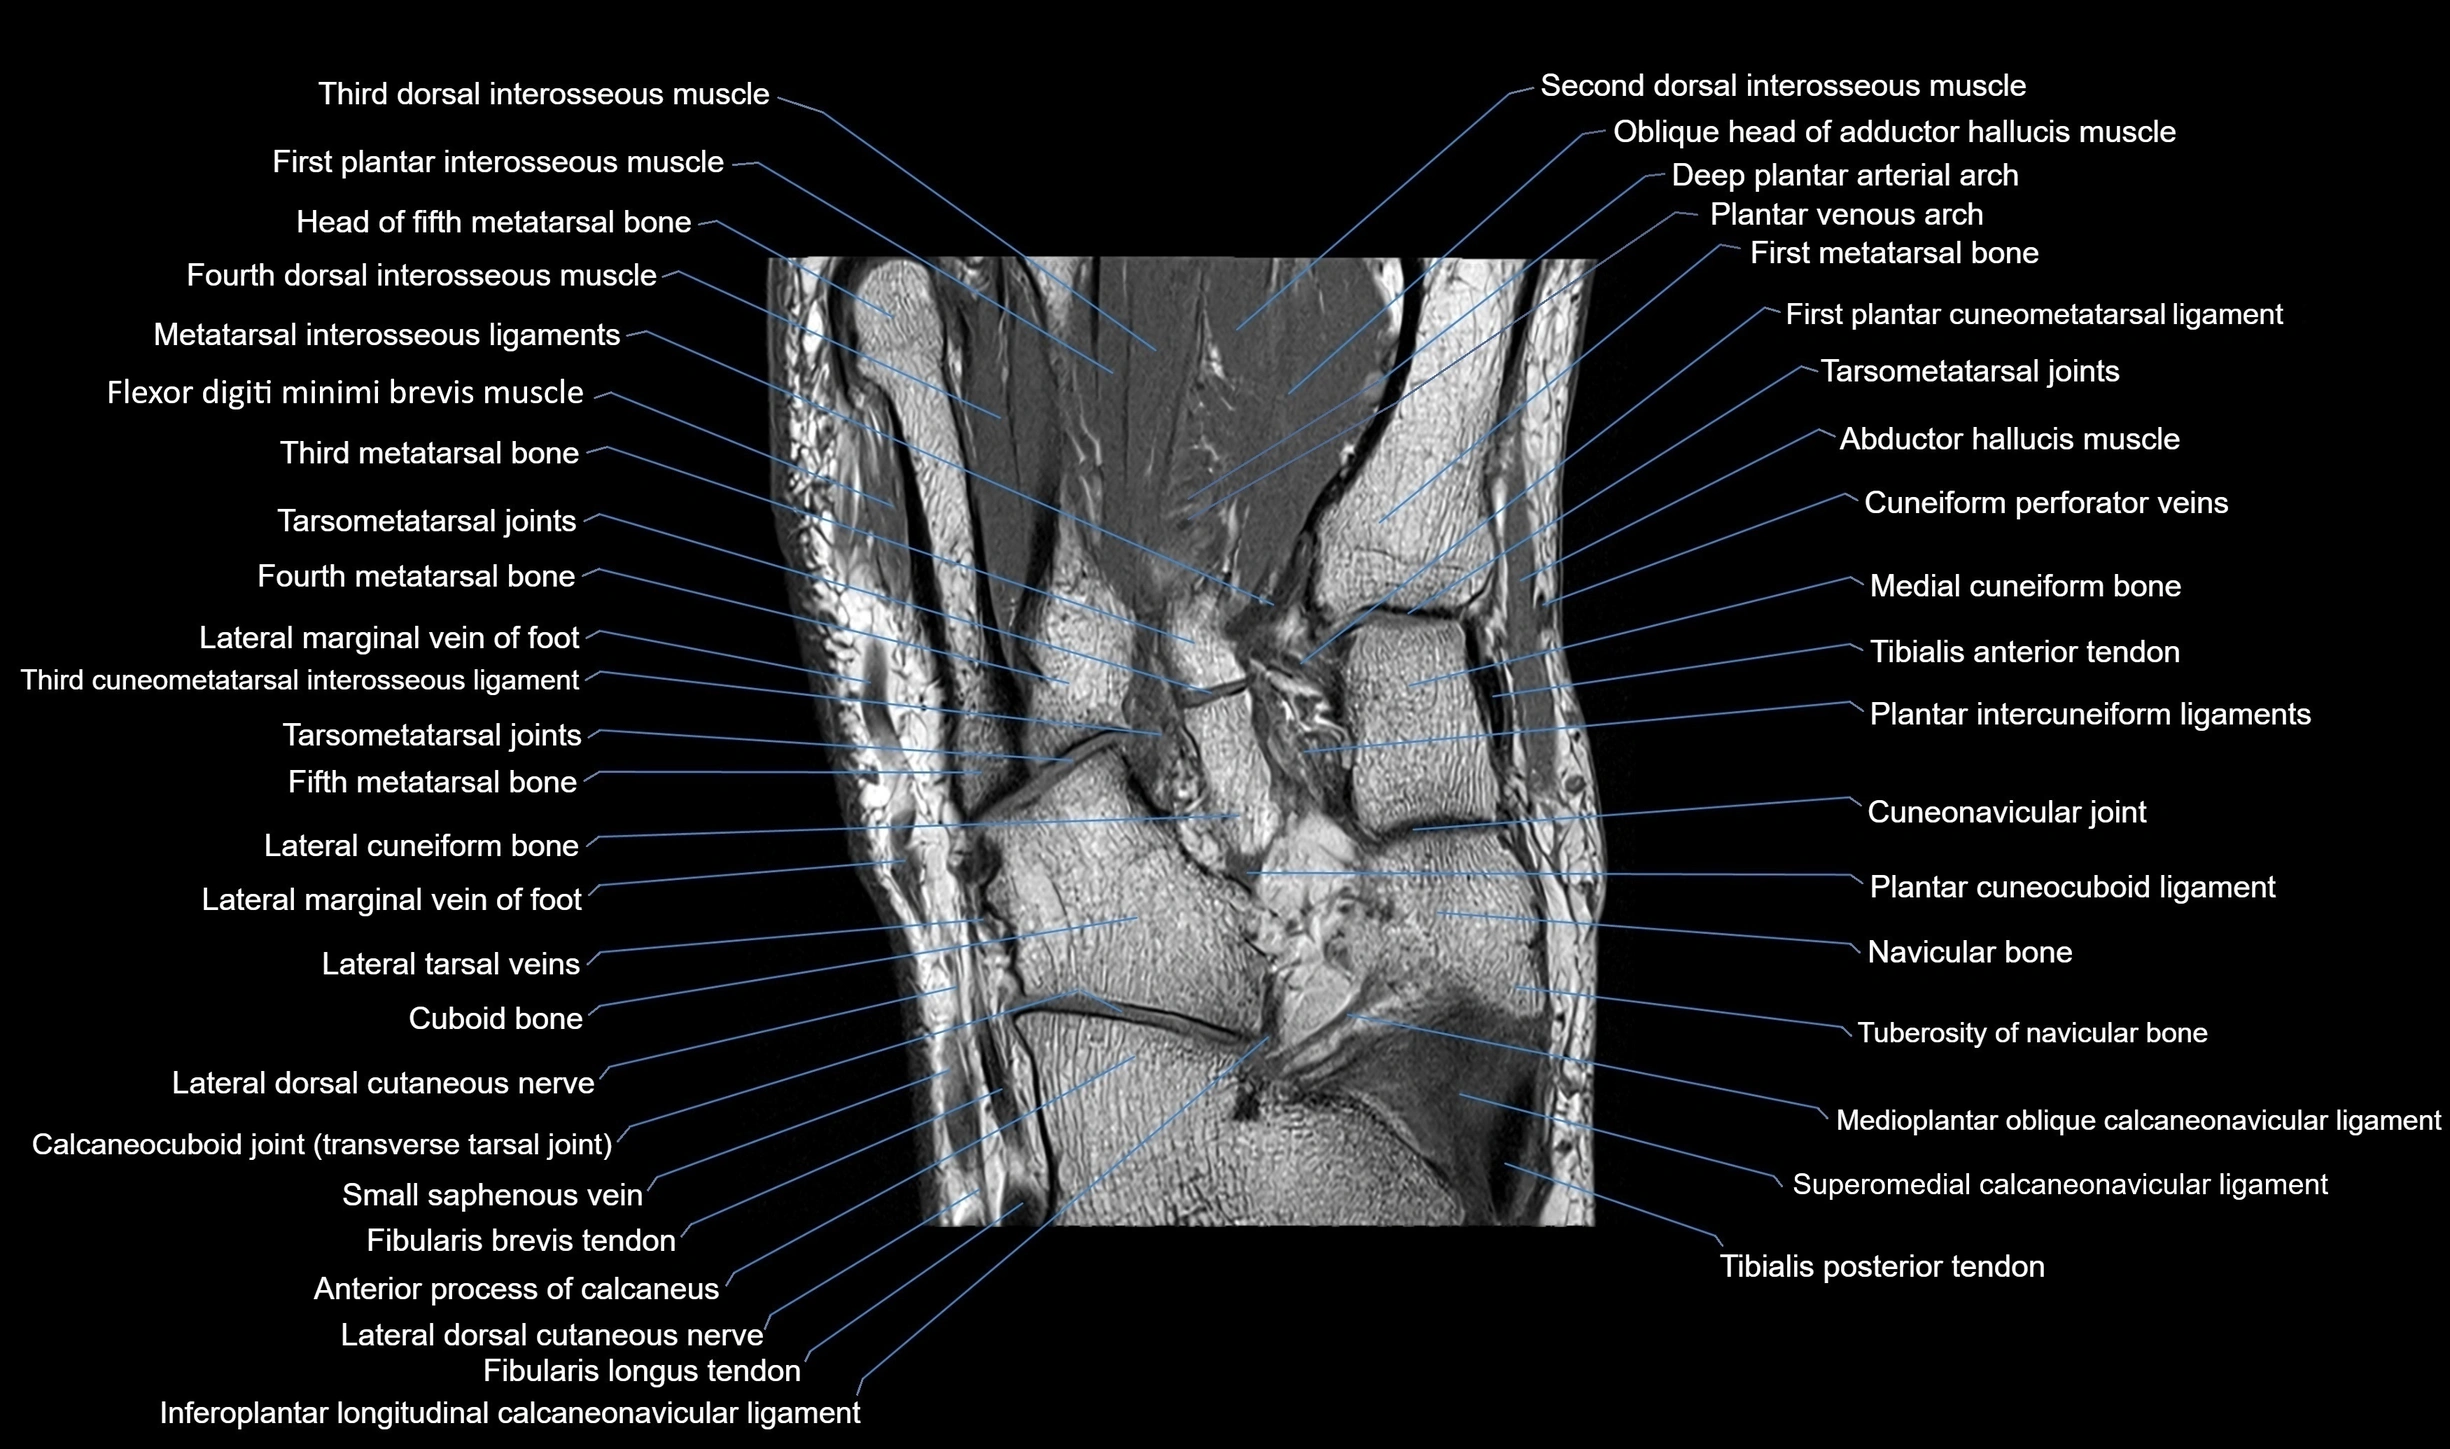

MRI image